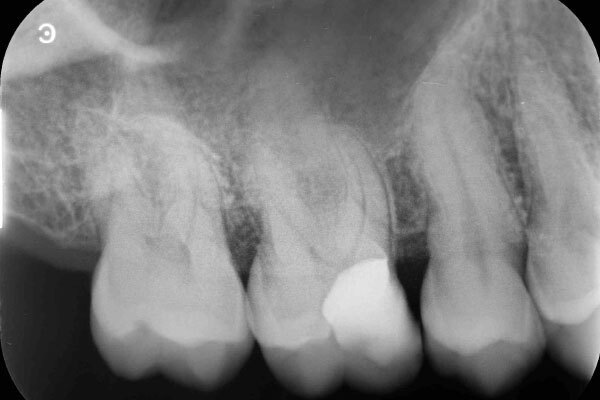

術前のデンタルX線写真と口腔内写真です。右上の前から6番目の歯(#26)です。

術前の診査で、神経が正常に生きていることが分かったので、なるべく神経を温存する治療を進めていくこととしました。

術直後のデンタルX線写真です。

術後1ヵ月のデンタルX線写真です。

自覚症状はなく、レントゲン写真でも異常所見は認めません。